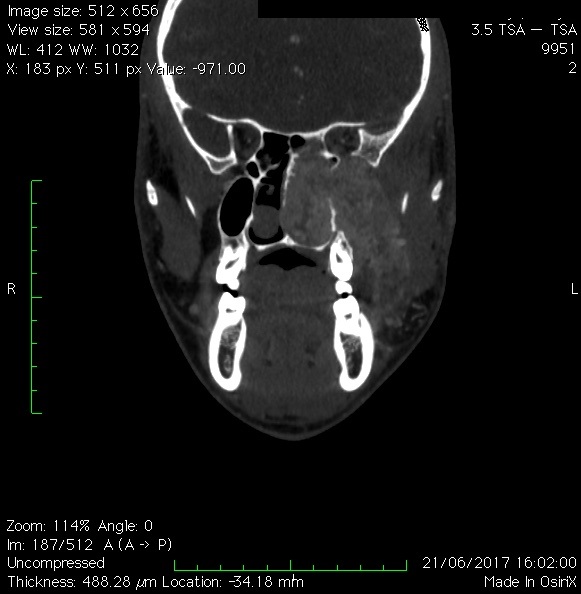

Les paragangliomes

Ce sont des tumeurs rares qui se forment près de l’artère carotide, la veine jugulaire ou le long des voies nerveuses de la tête et du cou. Certains paragangliomes sécrètent des catécholamines – des hormones produites habituellement par les glandes surrénales – appelée adrénaline et noradrénaline. La libération de ces catécholamines dans le sang peut provoquer des symptômes tels que hypertension artérielle, maux de tête, transpiration, rythme cardiaque rapide ou irrégulier, pâleur et tremblements.

Les paragngliommes peuvent être de deux types : sporadiques, ou familliaux. Dans ce dernier cas ils touchent plusieurs personnes de la même famille, surviennent chez des patients plus jeunes et sont souvent multiples.

Le traitement consiste habituellement en l’exérèse complète de la tumeur par le chirurgien ORL.

Localisation d’un paragangliome du foramen jugulaire (d’après Jackler, ATLAS OF SKULL BASE SURGERY & NEUROTOLOGY. Thieme. ©2009 )

Les tumeurs Glomus jugulaire sont rares. Il s’agit de tumeurs à croissance lente qui commencent dans l’os temporal (os de l’oreille) et se propagent à travers l’oreille. Les symptômes les plus courants sont des acouphènes pulsatiles ou une perte auditive. La tumeur peut se propager par la suite vers le cerveau, le nerf facial et l’oreille interne, affectant l’audition et de l’équilibre.

Ces tumeurs sont traitées chirurgicalement par les membres de l’équipe ORL ou par radiochirurgie stéréotaxique si elles sont très petites.